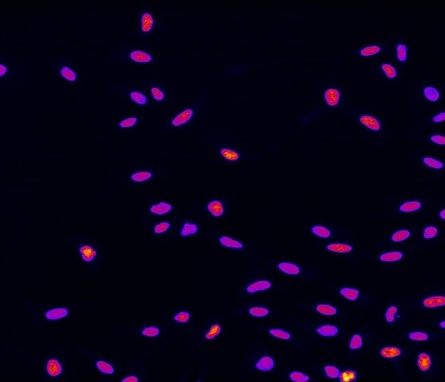

This groundbreaking form of personalized cancer immunotherapy has had remarkable success — more than 45,000 cancer patients worldwide have been treated with CAR T-cell therapy, extending their lives and, in many cases, delivering complete and sustained remissions.